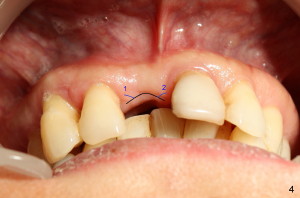

Fig.4 shows incision design for implant uncover (following osseous surgery in the upper right quadrant). The main incision is indicated by black line, lingual to the crest so that the buccal flap is more bulky. It is curved and festooned to create the future cosmetic buccal gingival margin. If the main incision is placed too lingual to expose the implant, one or two accessory incisions (red) can be made. After insertion of 4x6.5 mm non-shouldered abutment 3 mm post, PVS impression is taken. Fig.5 shows temporary crown in place (T) with two vertical mattress suture in the mesial and distal papillae. Two accessory incisions are approximated. Two weeks later, the temporary crown is removed. The accessory incision #1 has healed, while #2 is healing (Fig.6). The temporary crown helps form a nice socket around the abutment (A). Fig.7 shows the gingiva around the crown (to be cemented) with healing incision #2. Five months after crown cementation, the gingiva looks healthy.